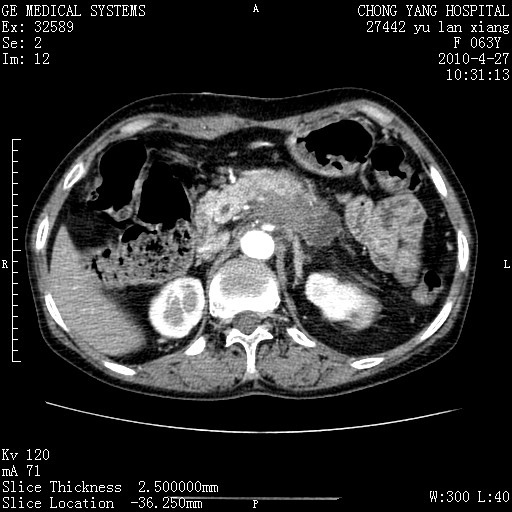

标题: CT26066:F63Y 上腹正中压痛半月,CA199:7400u/ml,MR示胰腺炎伴 [打印本页]

胰腺癌侵犯腹腔动脉干-分支、胃壁、左侧膈肌伴胰周及腹膜后淋巴结转移、胆囊切除术后。

胰腺癌侵犯腹腔动脉干-分支、胃壁、左侧膈肌伴胰周及腹膜后淋巴结转移、胆囊未显影。